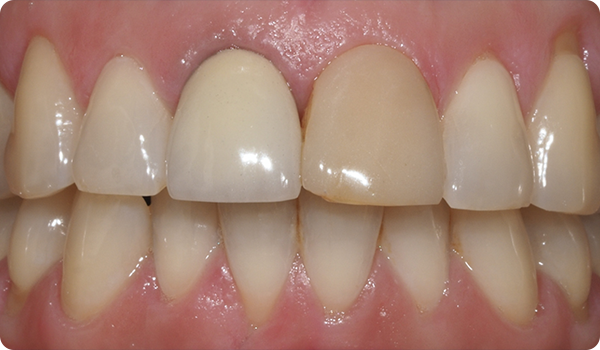

Designet til protetikere. Med små bevægelser korrigeres malpositioner og forbereder den mest egnede og konservative æstetiske behandling for dine patienter.

Med Right får dine patienter det smil, de ønsker, inden for den ønskede tid, på en komfortabel og "usynlig" måde.

At justere tænder med Right er den perfekte og mest skånsomme forberedelse til fremtidig tandblegning eller facadebehandlinger, der vil perfektionere patientens smil.